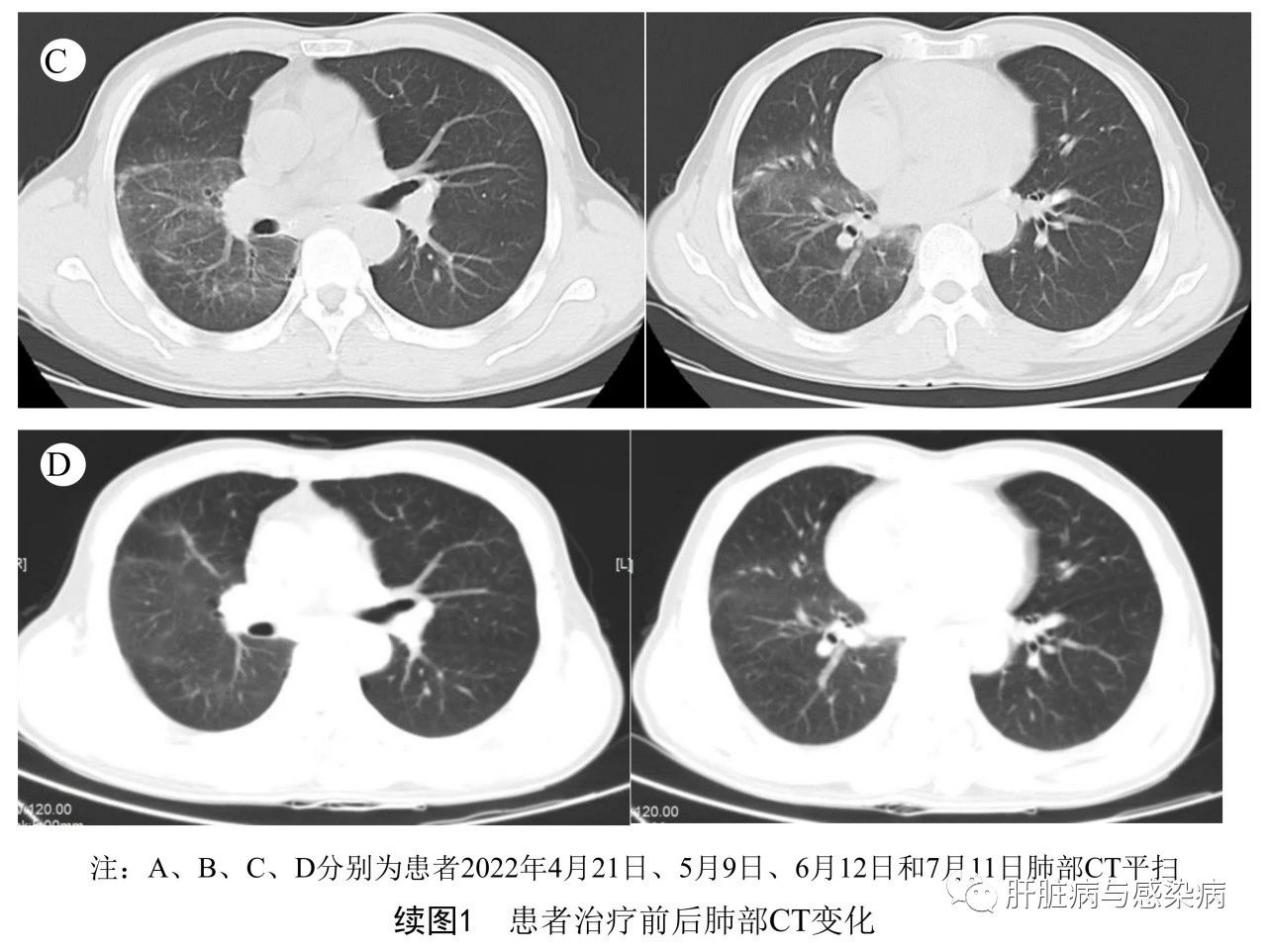

(2)影像学检查:4月21日:头颅 + 肺部CT示:脑干腔隙灶?考虑右肺大叶性肺炎;左下肺后基底段纤维灶;右侧胸腔少量积液(图1A)。

5月2日和5月9日肺部CT示:肺内病灶较前减少(图1B)。

第12天患者病情稳定,转至呼吸内科继续治疗,后续动态复查肺部CT示病灶较前吸收,并于5月12日办理出院,同时嘱其继续口服多西环素2周。出院第5天电话随访,患者呼吸道症状基本缓解。6月12日返本院复查血常规和肝肾功能均正常,血淀粉酶159 U,仍无腹痛腹胀、无恶心呕吐,本次复查(图1C)和7月11日(图1D)复查肺部CT均逐步改善。